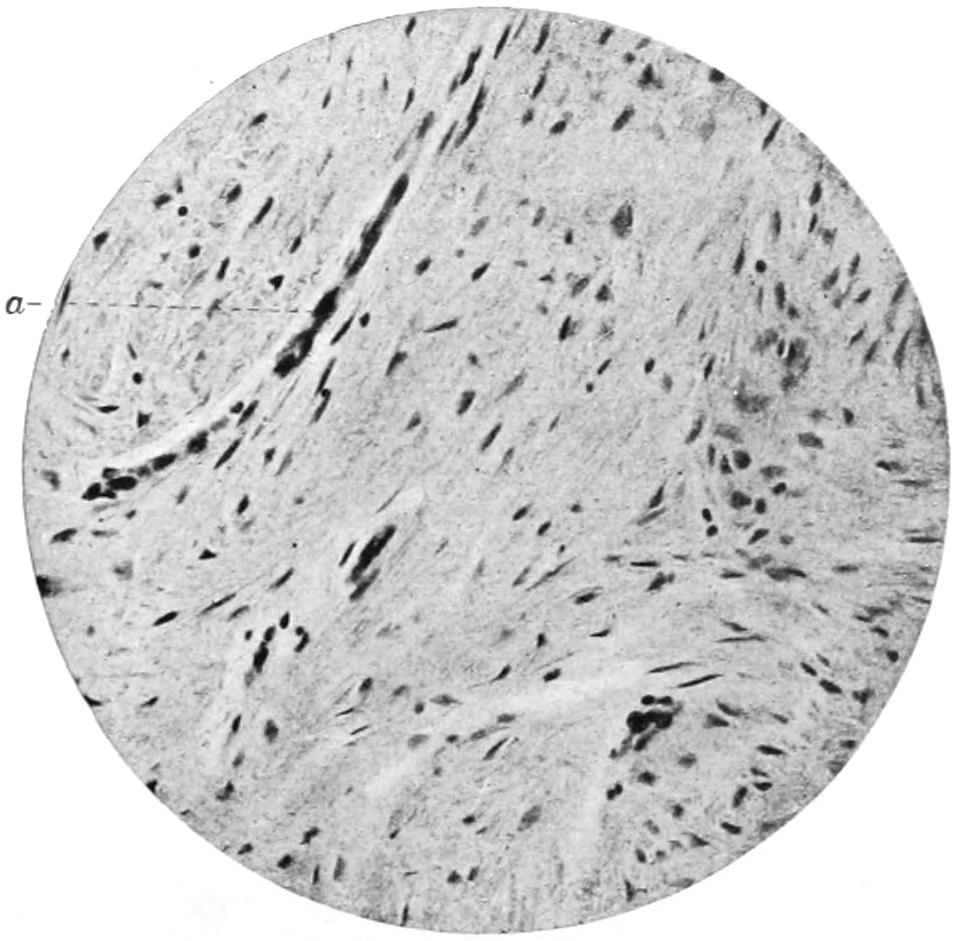

PLATE I

PLATE I.

BLOOD.

(Ehrlich triple stain.)

Fig. I. TYPES OF LEUCOCYTES.

a. Polymorphonuclear Neutrophile. b. Polymorphonuclear Eosinophile. c. Myelocyte (Neutrophilic). d. Eosinophilic Myelocyte. e. Large Lymphocyte (large Mononuclear). f. Small Lymphocyte (small Mononuclear).

Fig. II. NORMAL BLOOD.

Field contains one neutrophile. Reds are normal.

Fig. III. ANÆMIA, POST-OPERATIVE (secondary).

The reds are fewer than normal, and are deficient in hæmoglobin and somewhat irregular in form. One normoblast is seen in the field, and two neutrophiles and one small lymphocyte, showing a marked post-hæmorrhagic anæmia, with leucocytosis.

Fig. IV. LEUCOCYTOSIS, INFLAMMATORY.

The reds are normal. A marked leucocytosis is shown, with five neutrophiles and one small lymphocyte. This illustration may also serve the purpose of showing the leucocytosis of malignant tumor.

Fig. V. TRICHINOSIS.

A marked leucocytosis is shown, consisting of an eosinophilia.

Fig. VI. LYMPHATIC LEUKÆMIA.

Slight anæmia. A large relative and absolute increase of the lymphocytes (chiefly the small lymphocytes) is shown.

Fig. VII. SPLENO-MYELOGENOUS LEUKÆMIA.

The reds show a secondary anæmia. Two normoblasts are shown. The leucocytosis is massive. Twenty leucocytes are shown, consisting of nine neutrophiles, seven myelocytes, two small lymphocytes, one eosinophile (polymorphonuclear) and one eosinophilic myelocyte. Note the polymorphous condition of the leucocytes, i. e., their variations from the typical in size and form.

Fig. VIII. VARIETIES OF RED CORPUSCLES.

a. Normal Red Corpuscle (normocyte). b, c. Anæmic Red Corpuscles. d-g. Poikilocytes. h. Microcyte. i. Megalocyte. j-n. Nucleated Red Corpuscles. j, k. Normoblasts. l. Microblast. m, n. Megaloblasts.

The value of a careful blood examination is well illustrated by Plate I, prepared by Dr. Irving P. Lyon, in which are displayed the alterations of greatest interest to the surgeon.